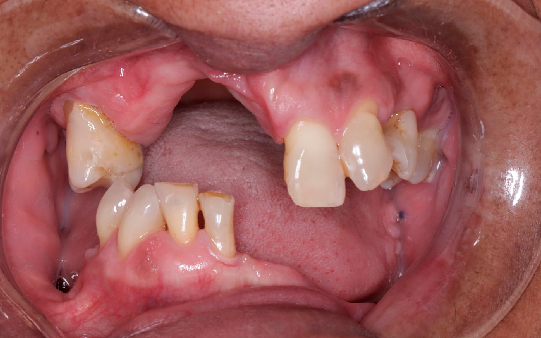

Baixa autoestima e dificuldade para sorrir

Problemas para se alimentar ou saborear alimentos